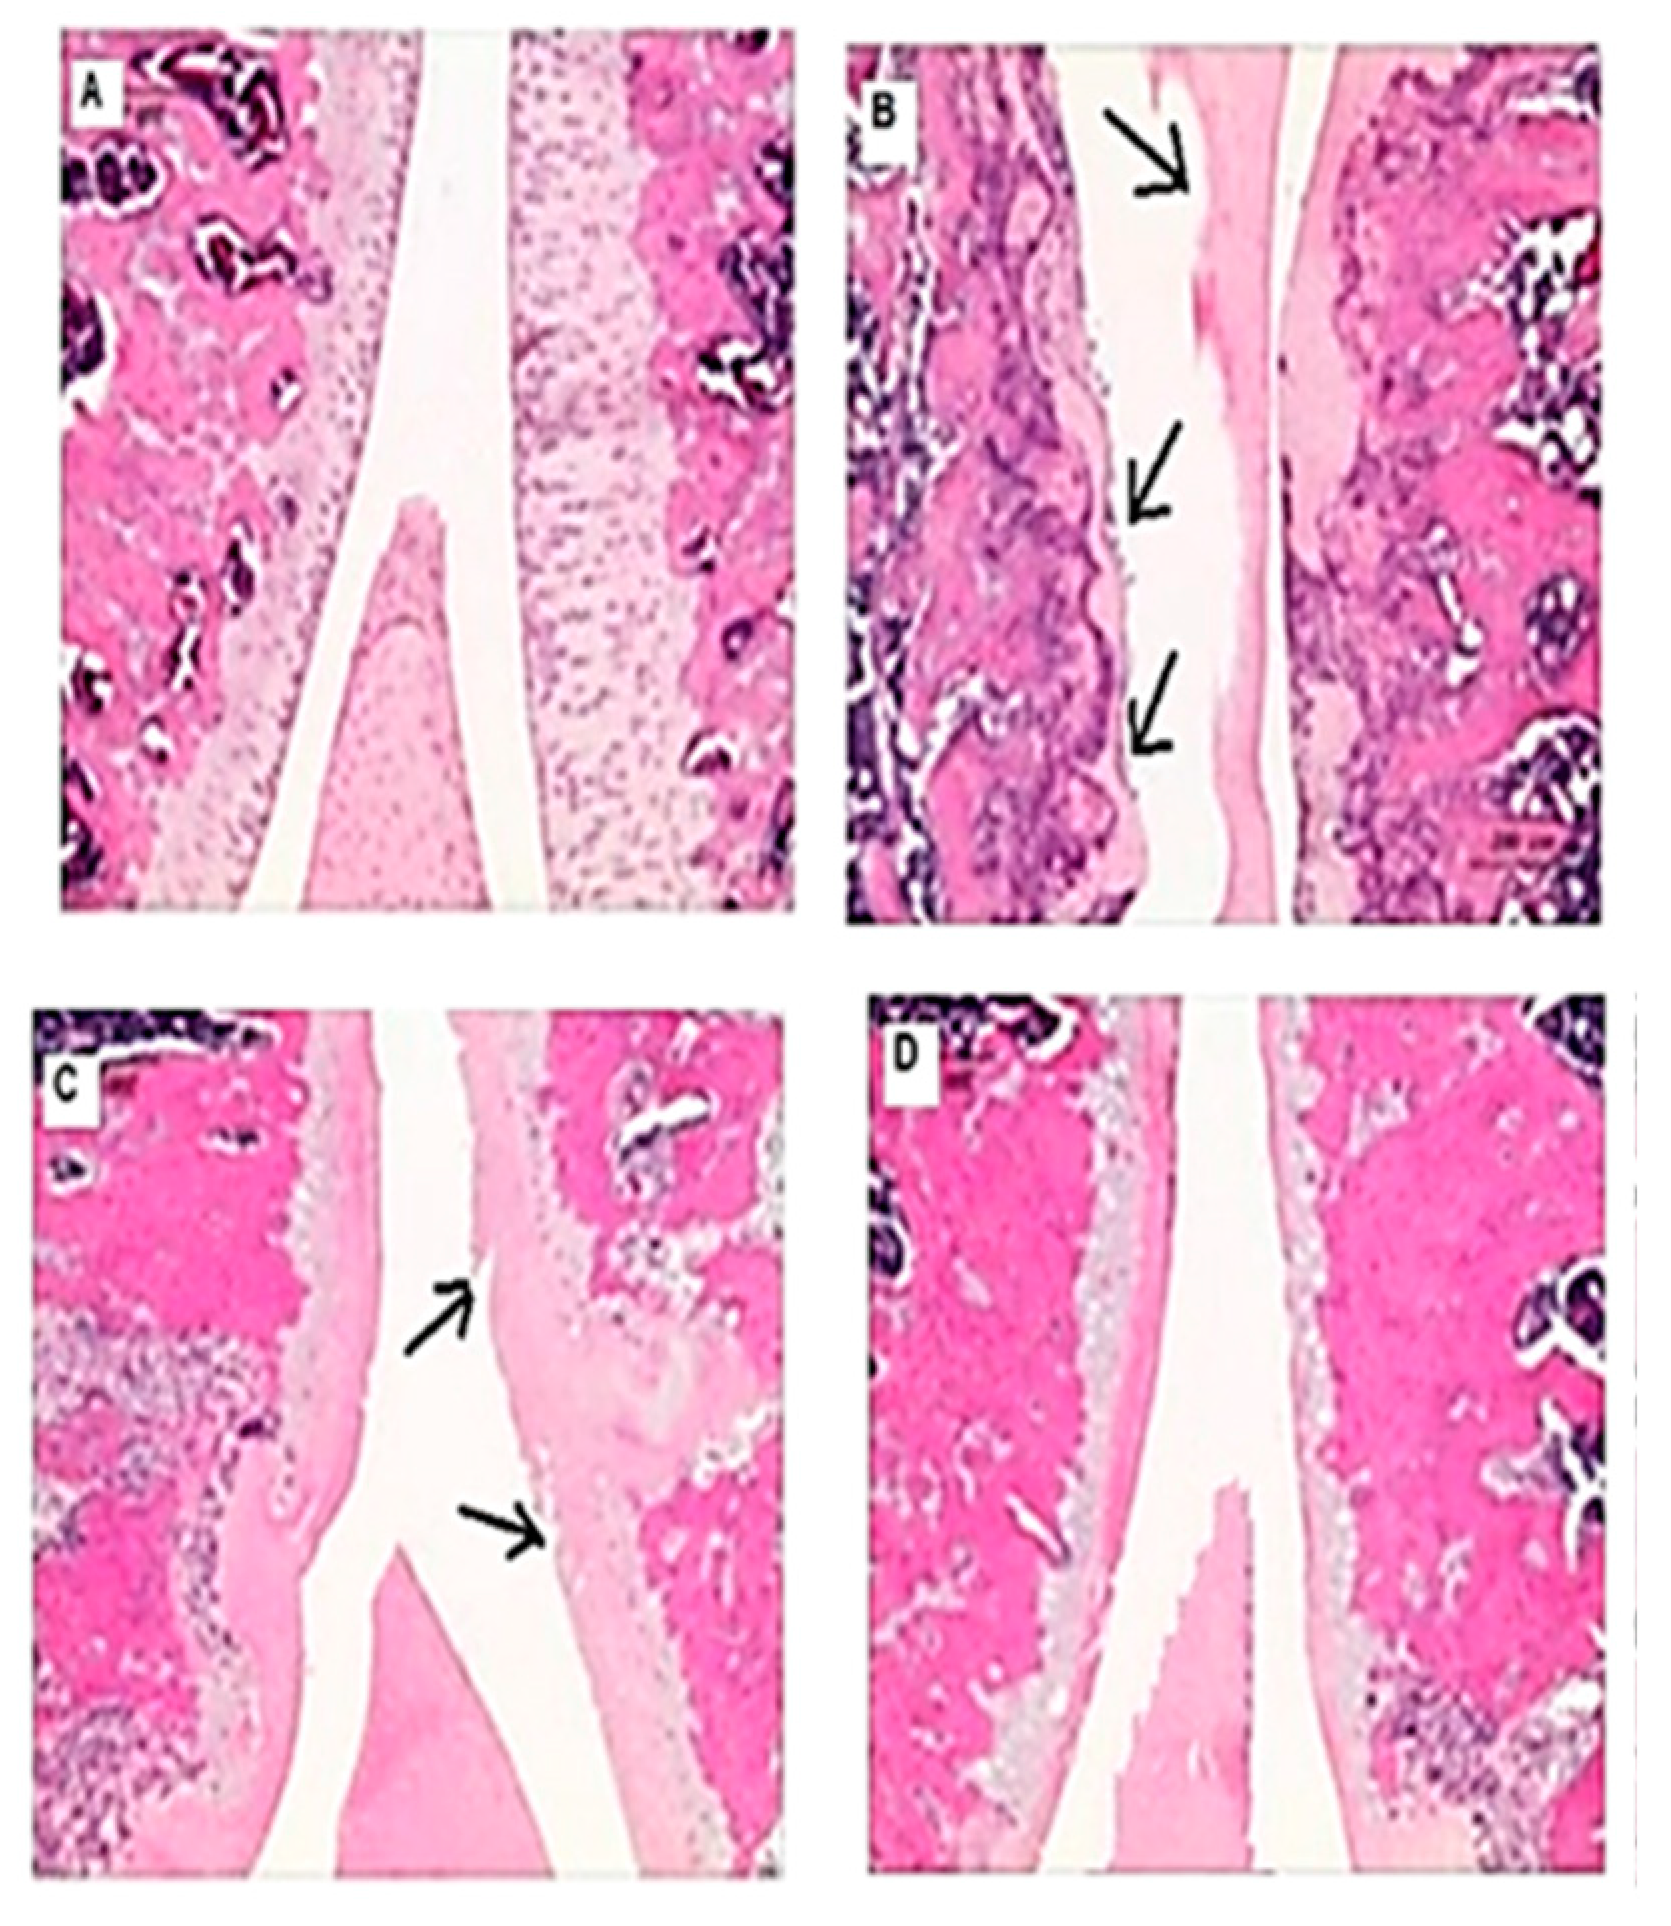

2.5. Histopathological Examination

3.5. Effects on the macroscopic apperance of the articular cartilage